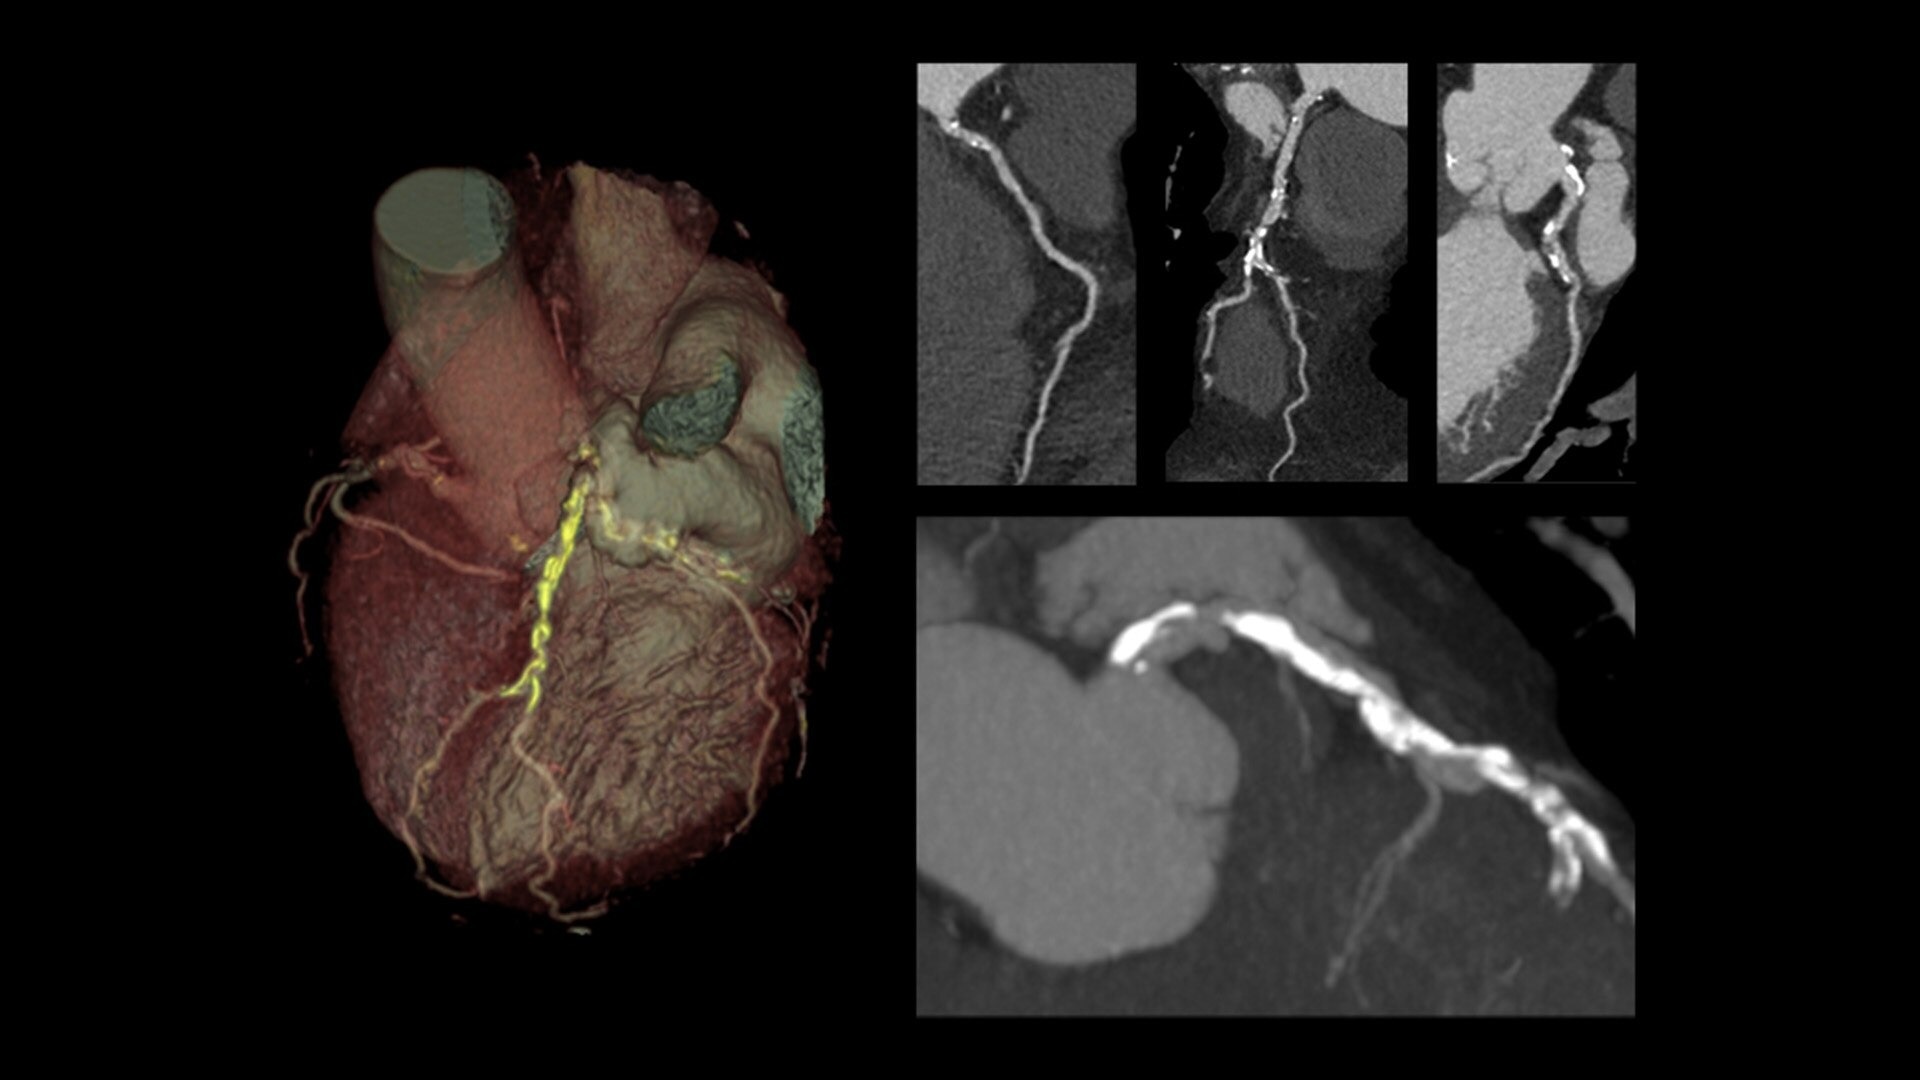

Snapshot Freeze 2 is an intelligent motion correction algorithm that's designed for coronary and valve motion correction, chambers, myocardium correction and great vessels motion correction.

ecg-less-cardiac-ct-4-ci-en